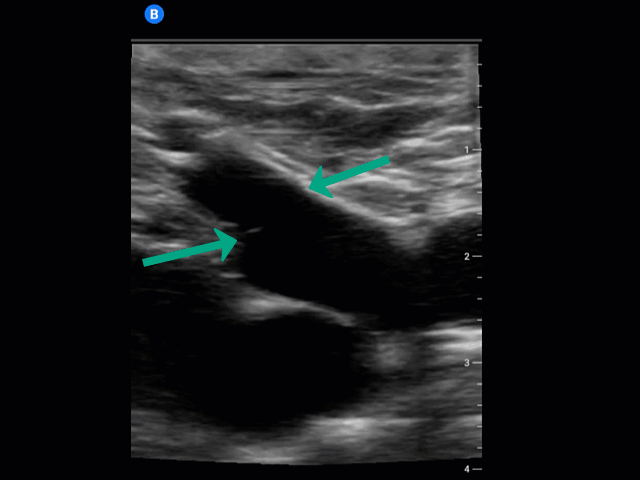

Valves: A common false positive for clot is the presence of a valve. This is a normal vein structure to prevent blood from refluxing backward. The green arrows show the attachment points of the valve between the greater saphenous vein and common femoral vein which appears a lacey hyper-echoic structure within the vessel lumen.